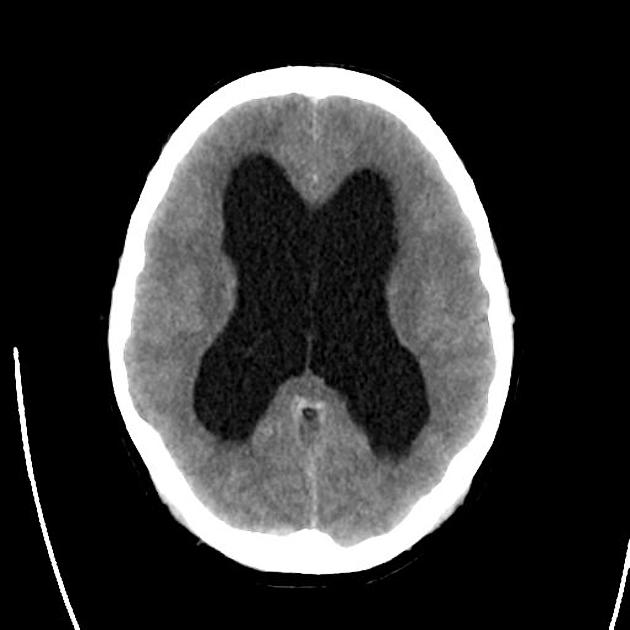

Example 4

Diagnosis

Hydrocephalus